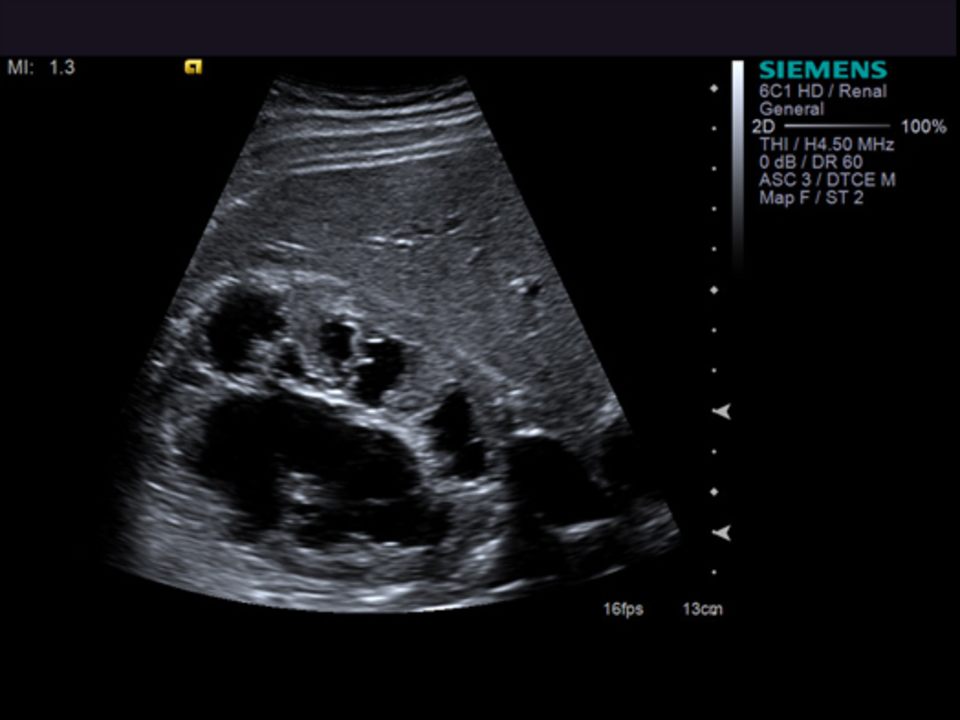

L'ecografia o ecotomografia è un sistema di indagine diagnostica medica che non utilizza radiazioni ionizzanti, ma ultrasuoni e si basa sul principio dell'emissione di eco e della trasmissione delle onde ultrasonore. Tale metodica viene considerata come esame di base o di filtro rispetto a tecniche di Imaging più complesse come TAC, imaging a risonanza magnetica, angiografia. Nelle mani del radiologo interventista è una metodica che può essere utilizzata per procedure terapeutiche mini invasive. L'ecografia è, in ogni caso, una procedura operatore-dipendente, poiché vengono richieste particolari doti di manualità e spirito di osservazione, oltre a cultura dell'immagine ed esperienza clinica. L'ecografia è una tecnica diagnostica che si serve degli ultrasuoni.

Può essere usato per esami quali; ecografia diagnostica, parti molli, tiroide, mammella, muscolo scheletrica, ecocolor dlopper, fibroscan, sonoelastografia